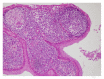

Lymphoepithelial cyst (LEC) is the most commonly encountered congenital neck pathology in the lateral part of the neck. A 66-year-old woman presented to the ENT clinic due to difficulty in swallowing persisting for approximately 1 year. Magnetic resonance imaging revealed a cystic mass at right tonsil. Surgery was performed due to this unilateral tonsillar mass, which was excised together with the right tonsil. LEC was diagnosed at histopathological examination. LEC in the palatine tonsil is rare, and only a few cases have been reported in the literature. We report a rare case of LEC in the palatine tonsil.